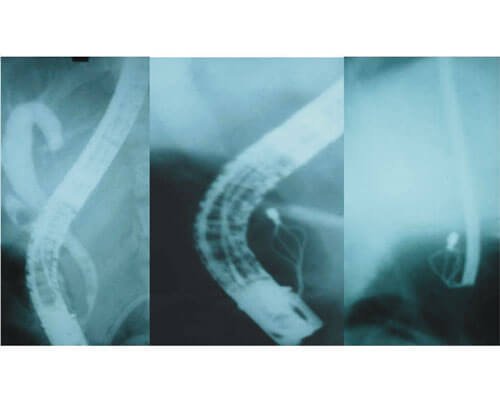

During ERCP stones can be removed form CBD or pancreatic duct and stents can be placed in CBD for treatment of jaundice and in MPD for pain relief

- Removal of common bile duct or pancreatic duct stones

- Chronic pancreatitis with stricture in the main pancreatic duct